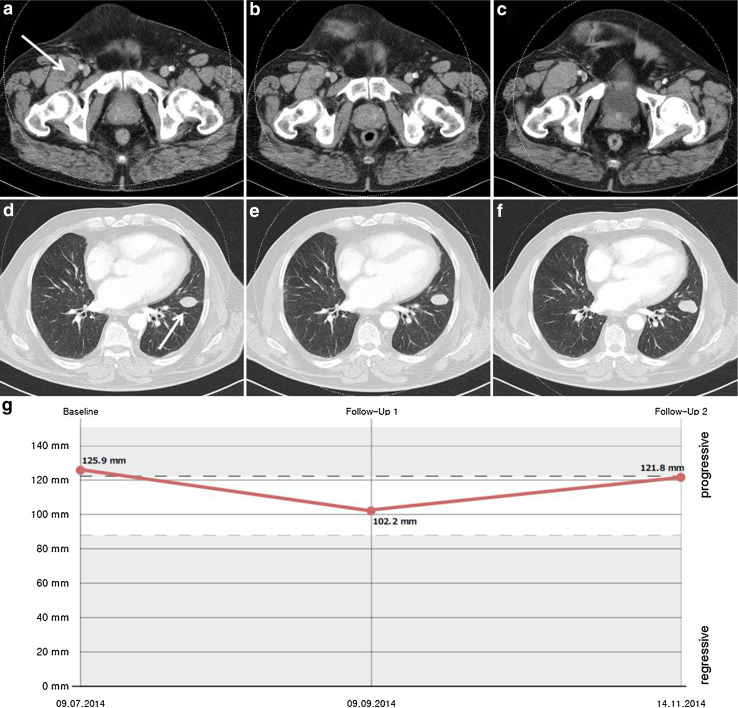

All seven patients (median age 63 years, range 36–69; five males, two females) had stage IV M1c disease based on the 2009 American Joint Committee on Cancer classification. Patient characteristics are listed in Table 1. Five patients had measurable disease when therapy was initiated, and two patients were treated in an adjuvant setting. Before therapy with rituximab, all patients had received several previous treatments. All had received ipilimumab. In addition, five patients had previously been treated with an anti-PD1 antibody, and one of the three patients with a BRAF V600 mutated tumour had already received pretreatment with a BRAF inhibitor. All patients completed the induction phase. Six patients received four cycles of weekly rituximab during the induction phase, and the first patient received eight cycles. First staging 8 weeks after the start of treatment revealed stable disease in five patients and progressive disease in two as best response to treatment. The most favourable course of the disease during the induction phase, an 18.8% decrease in tumour burden, was observed for the patient who received eight cycles of rituximab during the induction phase (Fig. 1).

Fig. 1.

Computed tomography scans of thorax and abdomen showing an exemplary target lesion in the left lung and a right inguinal lesion before therapy with rituximab (a, d), after the induction phase (b, e), and after three more cycles of maintenance therapy (c, f). The corresponding diagram shows the sum of target lesions (g)

Patients whose disease was stable after the induction phase continued the therapy. One patient received three additional cycles of rituximab, two patients received four more cycles and one patient received six additional cycles of rituximab until disease progression. One patient also underwent two surgical resections of subcutaneous metastases followed by adjuvant radiotherapy during the maintenance period. Median PFS was 6.3 months (95% CI 4.97–7.53). The patients who were treated in an adjuvant setting achieved the longest PFS (10.9 and 12.4 months). At the time of disease progression, progressive brain metastases were found in six patients. Consecutive therapies included resection of cerebral metastases, adjuvant whole brain radiation, stereotactic brain radiotherapy and radiotherapy for spinal metastases. Three patients received an anti-PD-1 antibody as a consecutive treatment, two patients received polychemotherapy and one patient was started on a BRAF inhibitor. One patient experienced progression of a gluteal metastasis and underwent radiotherapy. One patient’s disease progressed rapidly and further therapy was not feasible. Six patients have since died, and one patient was still receiving immunotherapy with an anti-PD-1 antibody in December 2016. Median OS (including subsequent therapy) was 14.7 months (95% CI 4.52–24.94).